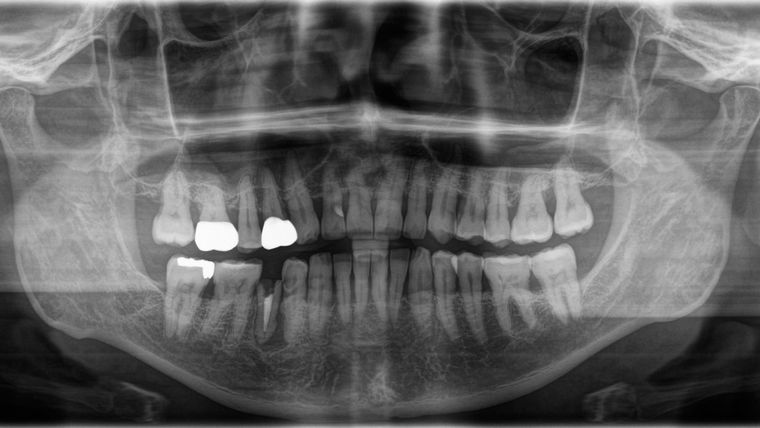

【体験レポート】抜くといわれた歯を残して再植治療(意図的歯牙再植)した体験談(その3)

前回、再植治療をおこなっているクリニックに、はじめて夫婦でいき、夫の割れてしまった歯の状態を検査してもらい、先生に治療方針を説明してもらった話を書きました。 前回の内容はこちら↓ 根管治療 今回は、再植治療にすすむための前段階としての根管治... -

【体験レポート】抜くといわれた歯を残して再植治療(意図的歯牙再植)した体験談(その2:初診)

近所の歯科クリニックで抜くしかないといわれた歯を再植(いちど抜いてまた移植する)治療することにした、うちの夫の体験を書いています。前回の内容は 「【体験レポート】抜くといわれた歯を残して再植治療した体験談(その1) 」こちら↓ 抜歯すること... -

【体験レポート】抜くといわれた歯を残して再植治療した体験談(その1)

うちの夫は、2022年9月、近所の歯科クリニックでもう抜くしかないですといわれた歯を、別のクリニックで「再植」という治療を受け、抜かずにすみました。厳密には一度抜くのですが、その歯をきれいに修復して、またそこに戻すという治療法です。 歯を失っ... -